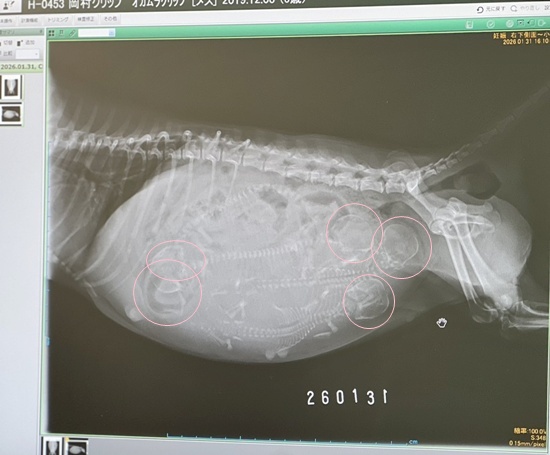

先日インスタではアップしてますが、クリップママの妊婦健診についてです。

メディカルチェックの結果、妊娠が発覚(ToT)

予定は大体2月の8~10日前後かと。

血液検査で貧血、心雑(Grade3/6)、パテラ、CRP(炎症反応値)など色々でしたが、ご飯をしっかり食べ、栄養が行き届いて来たようで、ママの体もふっくら、順調にお腹の子も成長しているようです。

そして、先日の妊婦健診。

レントゲンを撮ったのですが、小魚のような背骨と頭蓋骨が写ってます。

思ったより長めの骨です。

先生は頭の数は多分4匹と言われてましたが

どうも5匹に見えますが、皆さんはどうですか?

はっきり言って、少ないほうが助かります(ToT)